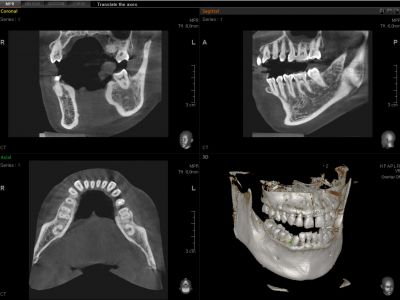

INNOVACIÓN INTELIGENTE PARA EL DIAGNÓSTICO EXACTO

La calidad de imágenes 3D ha mejorado dramáticamente gracias a la innovadora tecnología de reconstrucción de imagen.